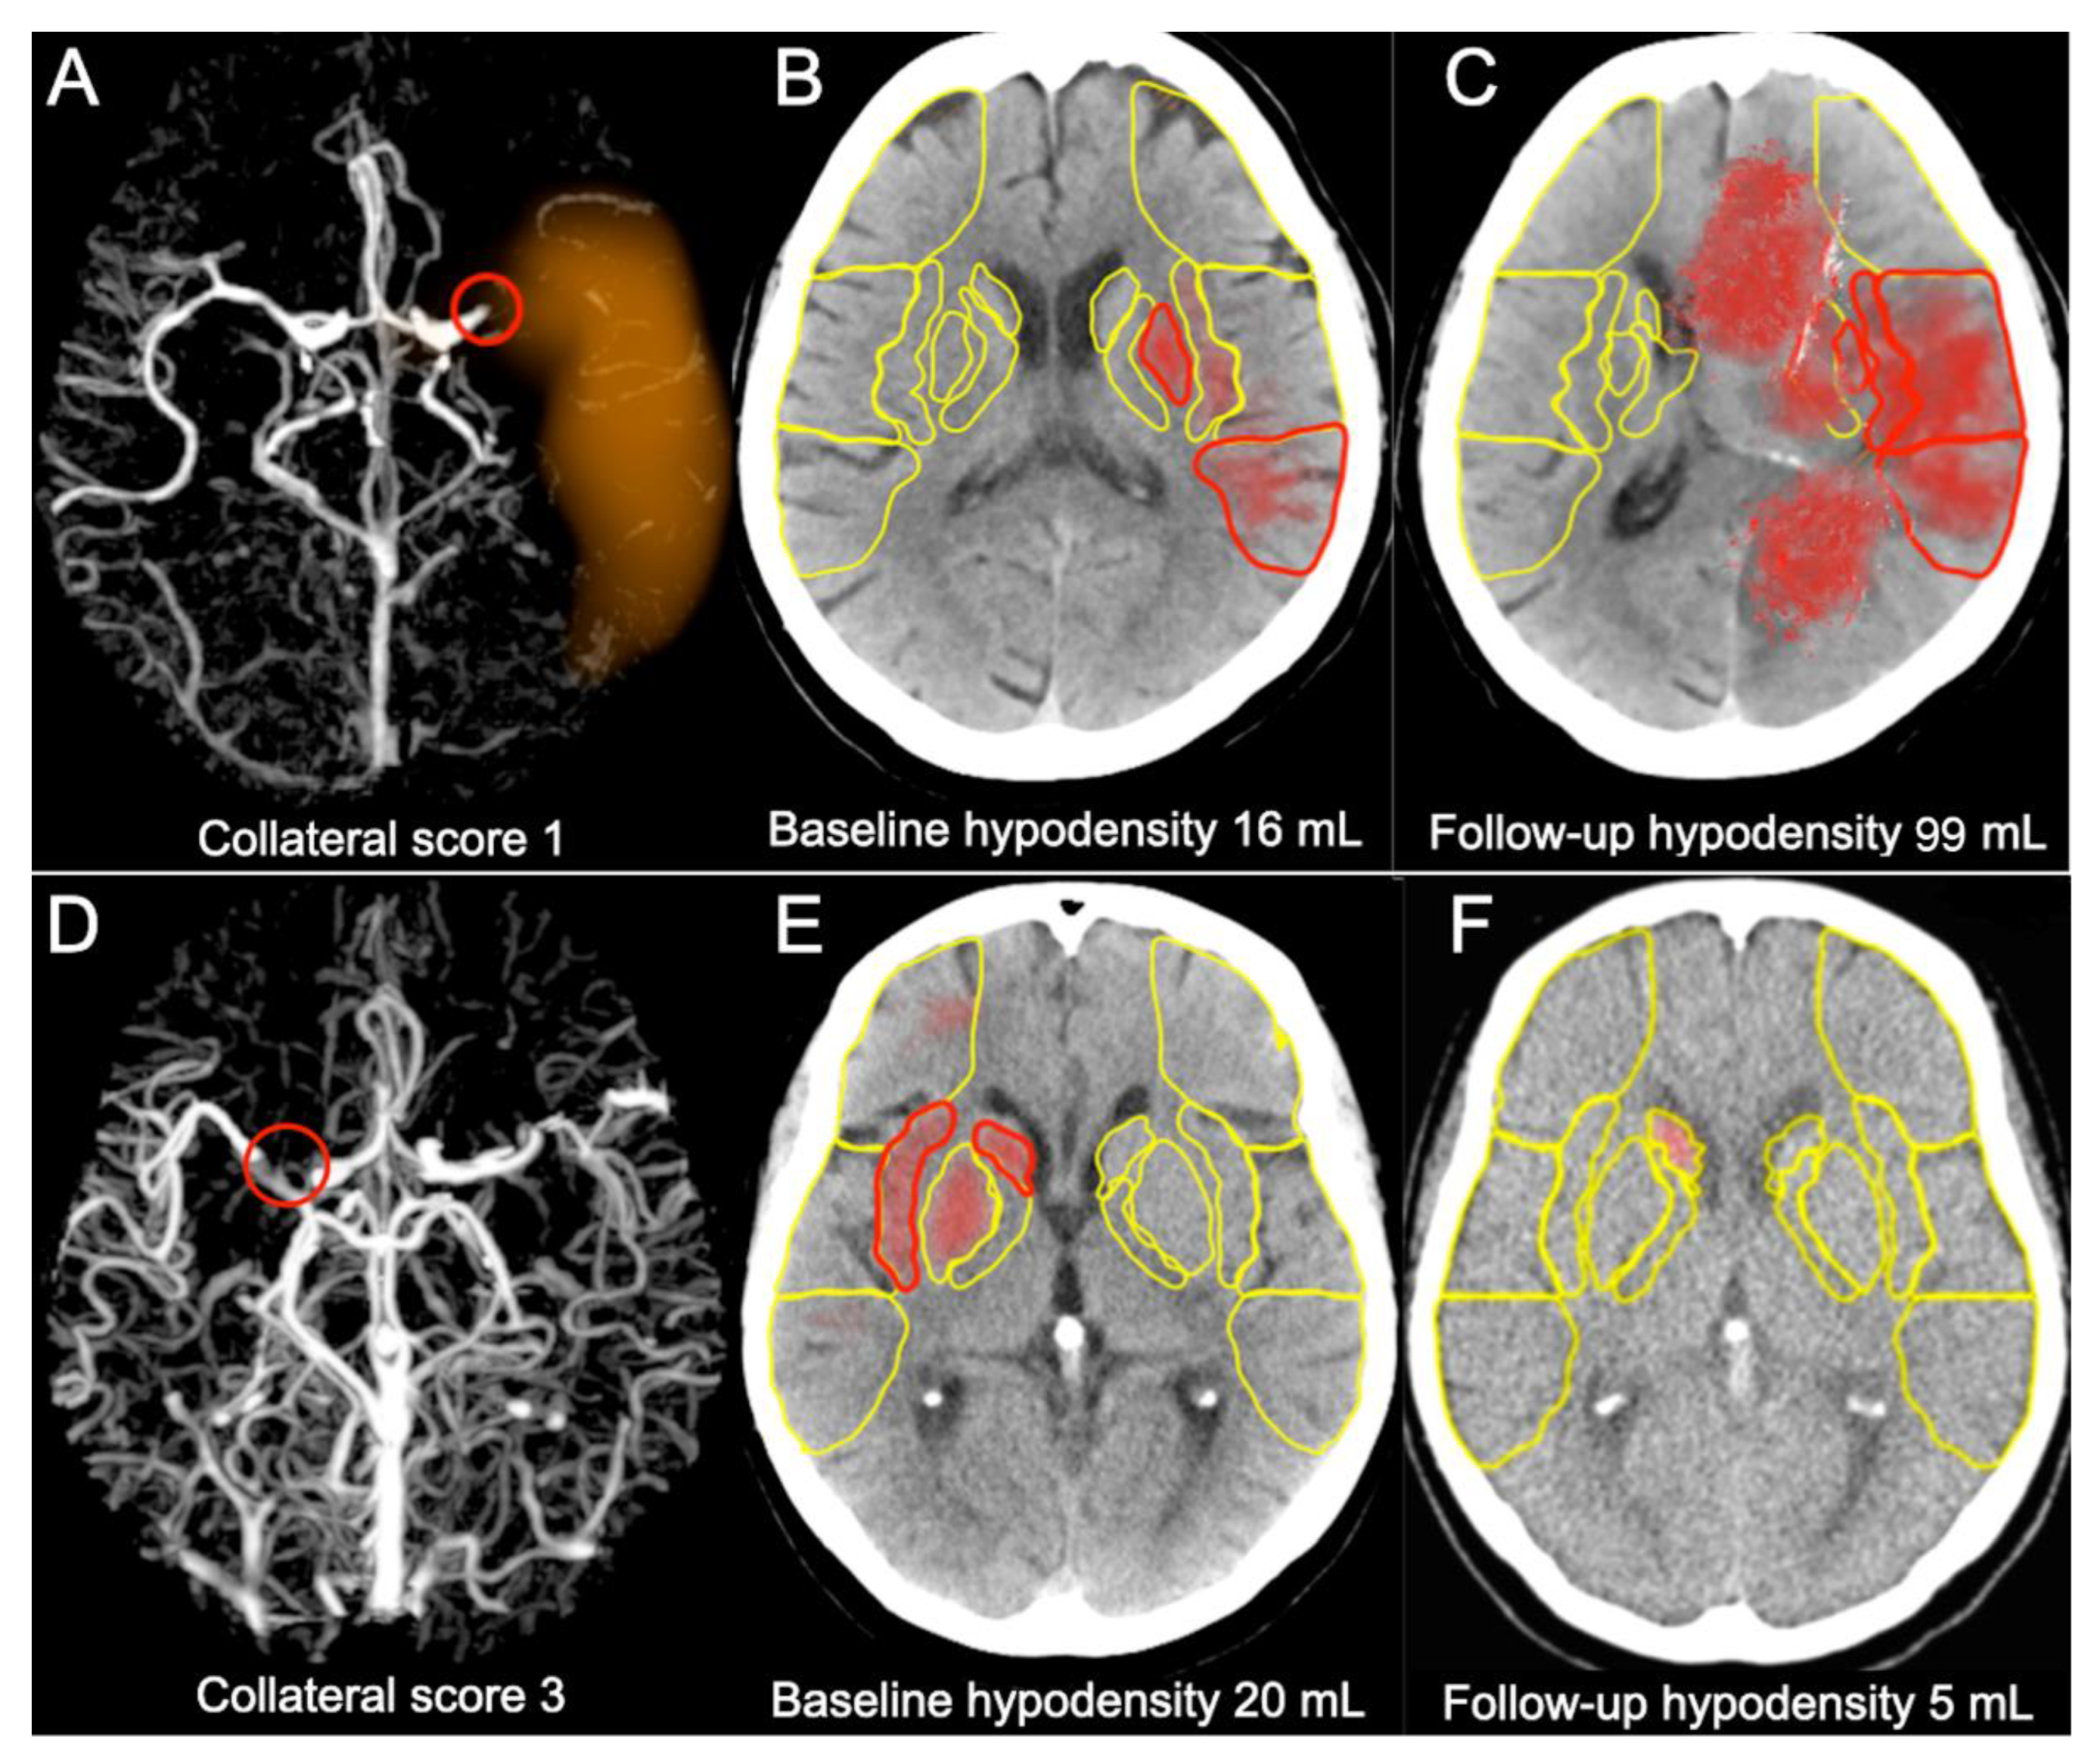

In the group with collateral Grade 3 the follow-up hypodensity volume appeared to be smaller than the baseline volume, and was absent in some cases. In the group with collateral Grade 2 there was a slight increase of the hypodensity volume and in the groups with collateral Grades 0 and 1 the increase was significant, as presented in Figure 2 and Figure 3. Representative cases are shown in Figure 4.

Figure 4. Representative cases with poor and good collaterals. Upper row presents the case of 79 y/o female treated 2 h and 43 min from onset of stroke with TICI 3. IVT was not administered due to the usage of oral anticoagulants: (A) left M1-MCA occlusion shown by red circle on timing-invariant CTA and poor collaterals scored as 1 by e-CTA; (B) e-ASPECTS assessed acute hypodensity volume for 16 mL on the baseline NCCT (red areas); (C) the follow-up NCCT revealed significant increase of hypodensity calculated for 99 mL by e-ASPECTS (red areas). Lower row presents the case of 72 y/o female treated 4 h and 50 min from onset of stroke with TICI 3: (D) right M1-MCA occlusion shown by red circle on timing-invariant CTA and good collaterals scored as three by e-CTA; (E) e-ASPECTS assessed acute hypodensity volume for 20 mL on the baseline NCCT (red areas); (F) the follow-up NCCT revealed significant decrease of hypodensity calculated for 5 mL by e-ASPECTS (red area). Regions used for calculation of ASPECTS are marked in yellow.